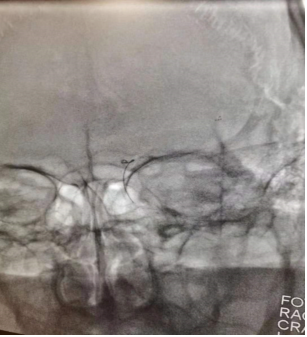

支架释放、EF远端通路导管到达颈内动脉末端,边抽吸边回收支架

拉栓后复查造影,血管通畅